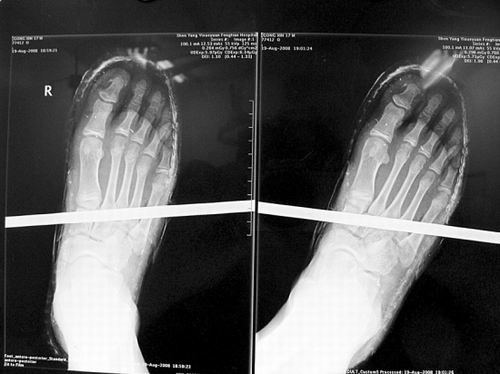

X光片顯示無大礙

事發(fā)時(shí)男孩穿著一雙布鞋,骨外二科陳賓醫(yī)生操起剪刀,將布鞋一塊塊剪掉。經(jīng)X光透視,醫(yī)生驚奇地發(fā)現(xiàn):男孩雖然被鋼筋穿透了右腳,但骨頭、大的血管和神經(jīng)都沒受任何傷害!

20日,記者從X光片子上看到,鋼筋避開了男孩腳掌骨頭密集的部位,而是從腳弓處穿過,這個(gè)部位基本上以軟組織為主。“真沒想到,太神奇了!”幾名醫(yī)生連聲感嘆,術(shù)中,他們分工合作,小心翼翼地將鋼筋取出,并做了引流、清創(chuàng)、包扎。